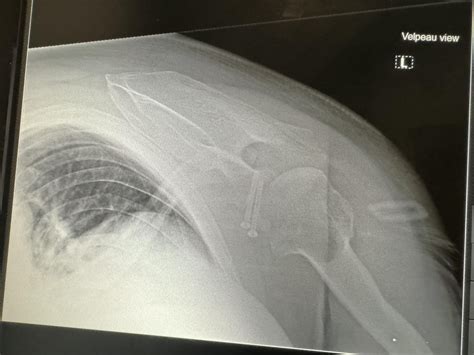

Shoulder X Ray

• Dislocations: If the humerus has popped out of the socket, an X-ray confirms the position of the bones and ensures no small fractures occurred during the incident.

Bone Displacement Indicates a dislocation or subluxation event.